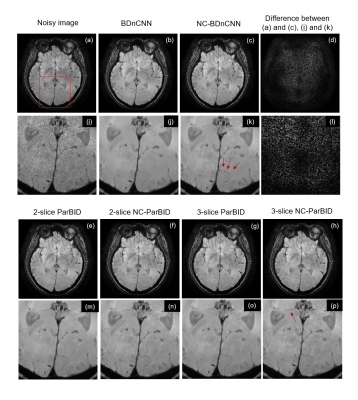

The results of application of ParBID are shown in Fig.4. The weight coefficients used for two or three slices were {{0.7,0.3},{-0.3,1.3}} and {{0.3, -0.8,1.0},{0.2,0.6,0.2},{1.0,-0.8,0.3}}[4], respectively. ParBID was most effective at 2.5% noise level. Proposed method was applied to experimentally obtained images (slice thickness 1.2 mm). The results are shown in Fig.5. The fine shading and contrast of the images are well preserved in NC-BDnCNN as pointed by red arrows shown in (c) and (k). The application of ParBID further enhances contrast preservation. In general, PSNR tends to decrease when image structure preservation is increased, but in our study, both noise reduction and structure preservation were satisfied.

Figure 5. Application of proposed method to experimentally obtained MR image.

Noisy image is (a). Sub images (b),(c),(e) through (h) are the denoised images using BDnCNN, NC-BDnCNN, 2-slice ParBID, 2-slice NC-ParBID, 3-slice ParBID and 3-slice NC-ParBID. Sub images (i) through (p) are the enlarged image of the above images.